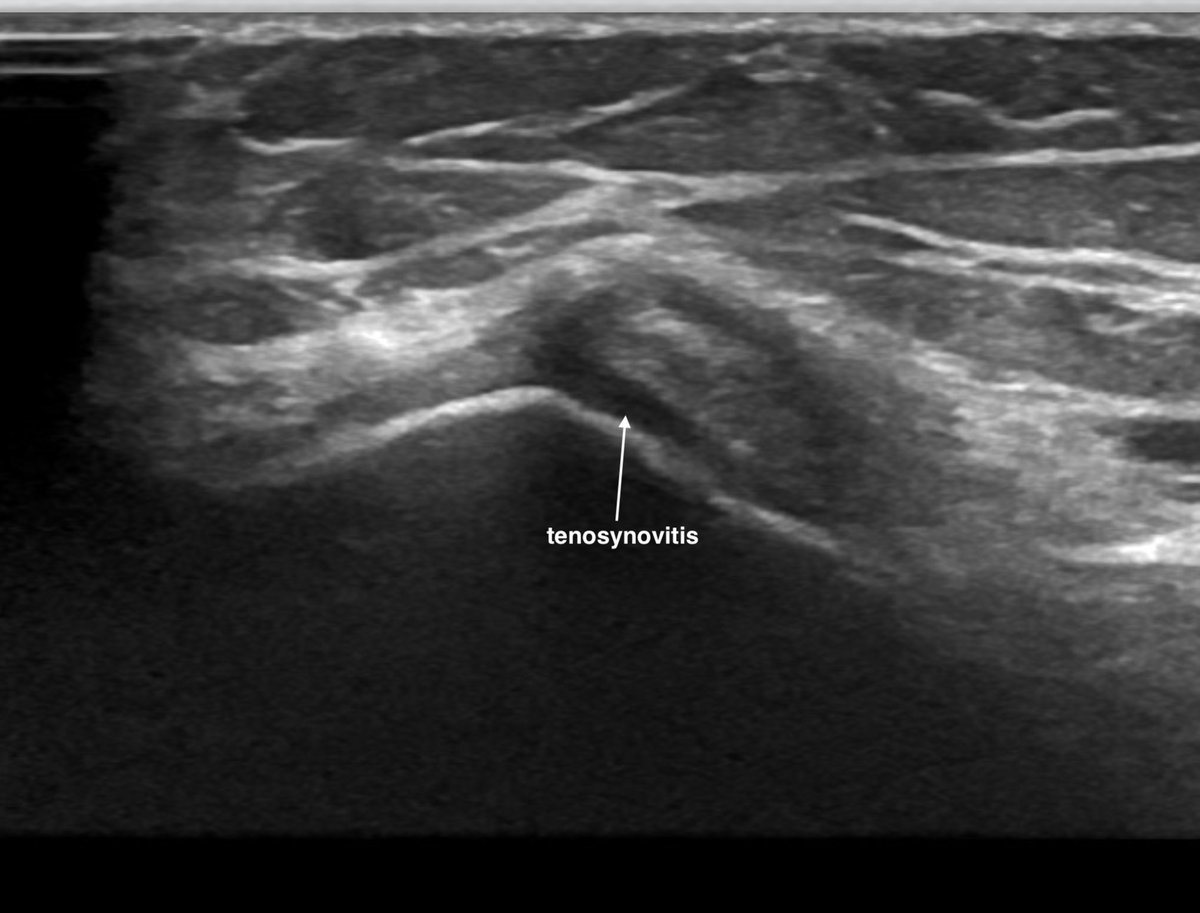

2. Meniscocapsular synovitis

Often seen in association with a meniscal tear or extrusion meniscopathy

If degenerate tear, incipient injury maybe unclear- sometimes just 🔼activity / load

US- astericks = inflammation; PD hyperaemia

External US guided CSi at meniscocapsular interface can be effective alongside 'standard' intra-articular injection ("inside & out")